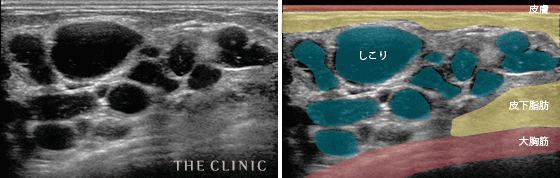

- 複数のしこりができてしまった症例